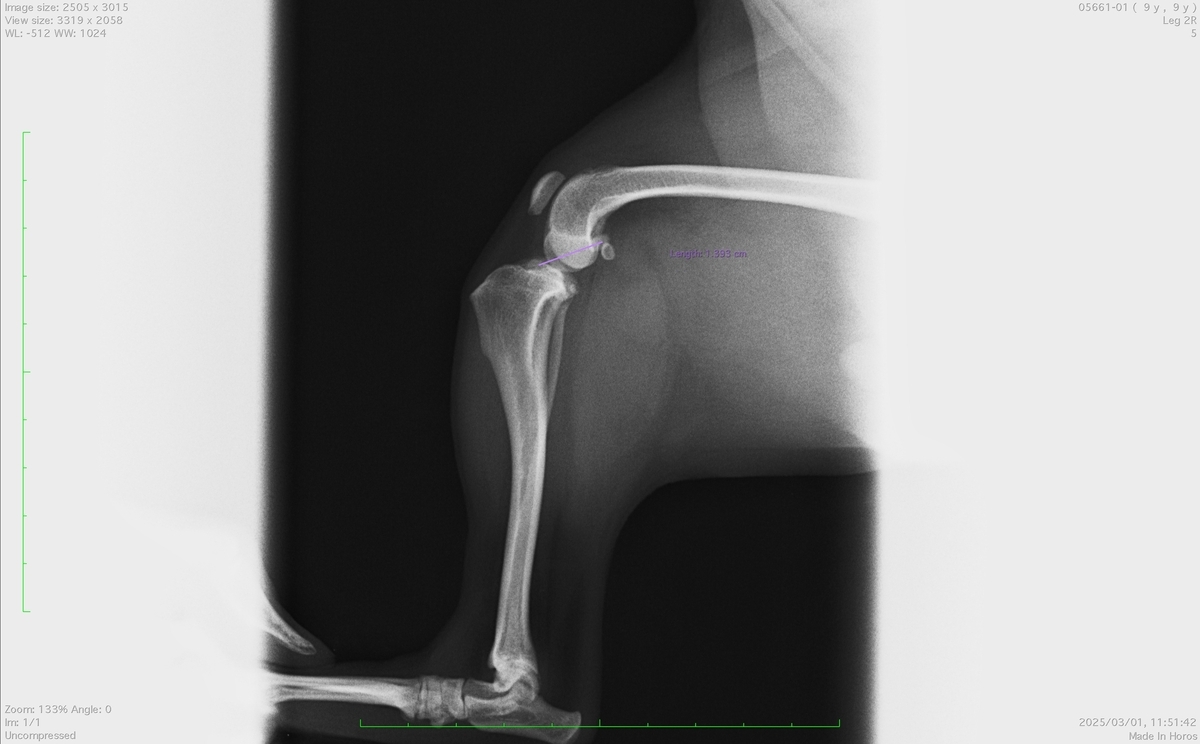

9歳の雑種犬(チワワ×プードル)で左後肢の跛行で来院されました。

触診とレントゲン写真で前十字靭帯断裂と診断しました。

左後肢の脛の骨が右足と比べて前方に変位しているのがわかります。